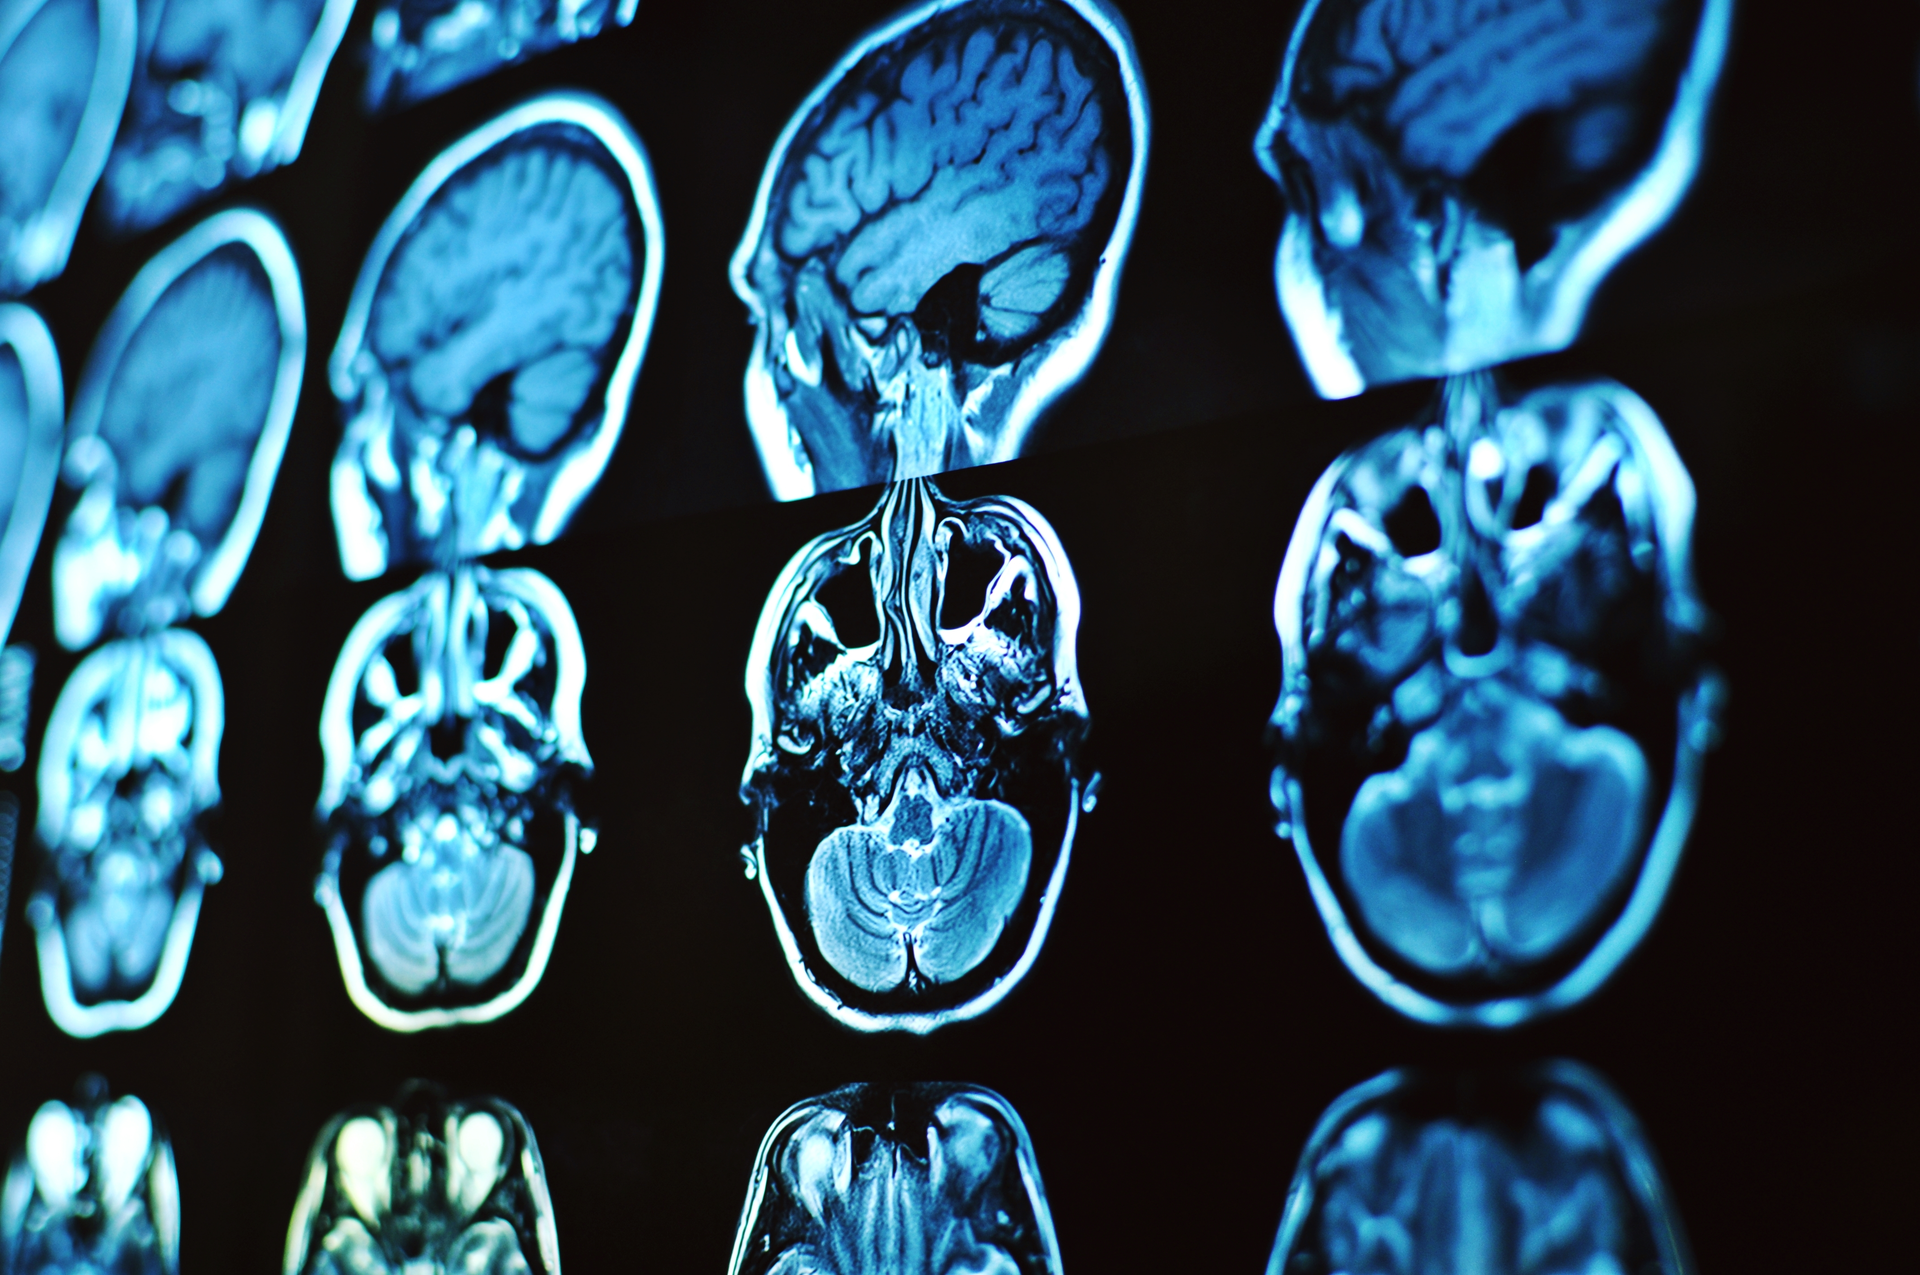

Researchers analyzing data from 51 middle-aged Pima American Indians living with type 2 diabetes used a series of memory and language tests developed by the National Institutes of Health, called the NIH Toolbox Cognitive Battery, as well as MRI, to determine the relationship between diabetes, cognition and makeup of the brain.

Brain imaging suggested that study participants with longer durations of type 2 diabetes had decreased mean cortical thickness and gray matter volumes, and an increased volume of white matter hyperintensities.

The MRI results, researchers say, indicate the negative effects longstanding diabetes may have on brain health outcomes and emphasize the importance of preventing early onset type 2 diabetes.